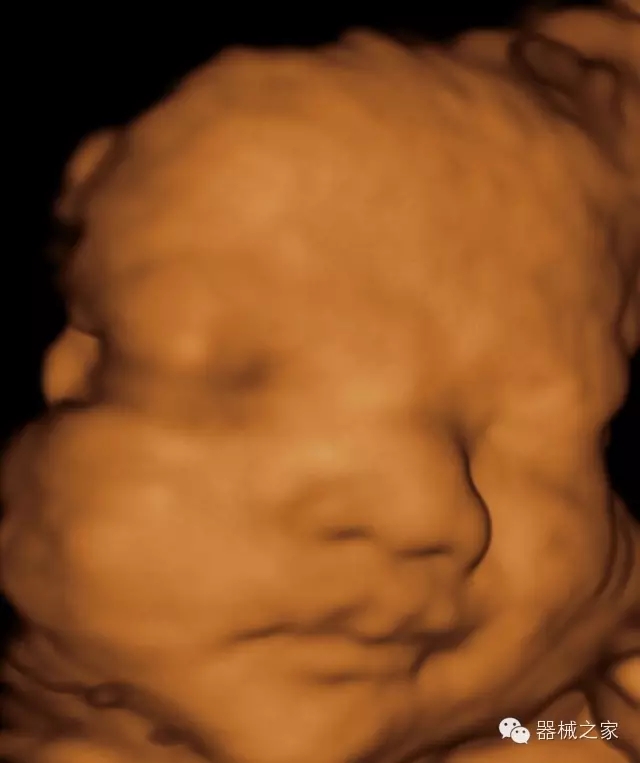

臨床圖片賞析

產(chǎn)品特點(diǎn)

·高效3D/4D成像技術(shù):高速的4D幀頻,豐富的3D成像模式,智能斷層切片功能;